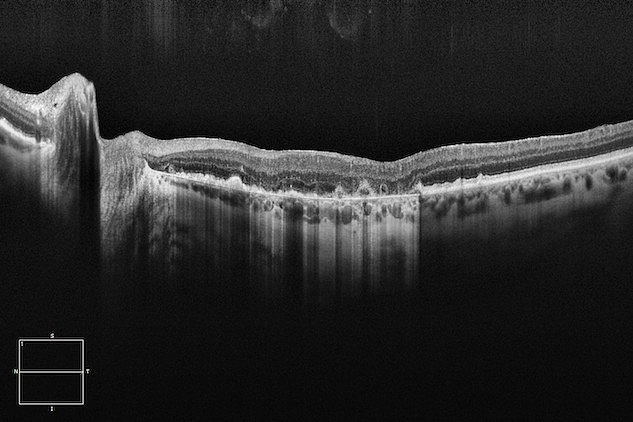

CIRRUS® from ZEISS is loaded with Advanced RPE Analysis*, which allows you to assess the integrity of the RPE and how it may have changed.

OCT has become indispensable. Learn how CIRRUS OCT with Advanced RPE Analysis can benefit your practice and assist you with the management of your patients.